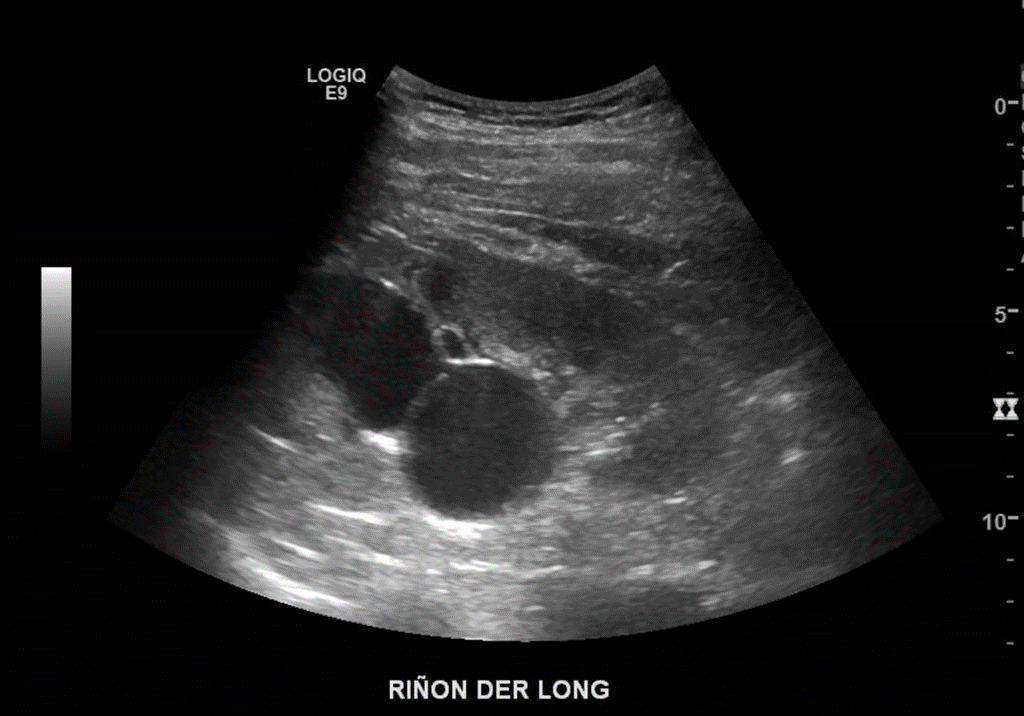

En riñón derecho, en sus tercios medio y superior, a nivel de seno y corteza, se observan 2 imágenes anecogénicas, redondeadas, de bordes bien definidos, con señal Doppler color y flujo turbulento al Doppler espectral. MAV’s vs Aneurismas.

Riñones en buena posición. Adecuado espesor cortical. No hay hidronefrosis. No hay imágenes de cálculos. En corteza renal derecha imagen de aspecto quístico de 37 x 24 x 37 m, con selectiva vascularización al modo Doppler y flujo turbulento. Adyacente otra, en seno renal, de similares caracteres, en 35 x 34 x 44 mm, también en corteza renal derecha quistes 15 mm, avascular.

Impresión Diagnóstica: Dos formaciones altamente vascularizadas en corteza y seno renal derecho, que ameritan correlación con tomografía computada multicorte.